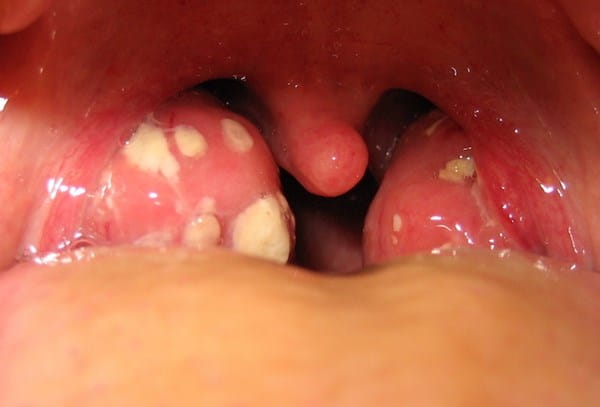

Inflamación de las encías y molestias en el paladar, bolitas blancas en la garganta

Doctor, que tal necesito su opinión por favor estoy desesperado, hace 7 meses tuve una infección muy fuerte en la boca con ulceras e inflamación de los ganglios y fiebre varios días y una lesión en el paladar que no podía comer, fui al doctor y me dieron antibióticos y medicina para los hongos y se me alivio, pero de ahí paa adelante me siguen saliendo úlceras pequeñas y se me quitan y tengo comezón en la garganta y se me inflaman las encías y se me alivia y se vuelven a inflamar y no se me quita al cien por ciento, aparte tengo dos bolitas blancas y no se me quitan en la garganta, por favor necesito que me ayude con su opinión